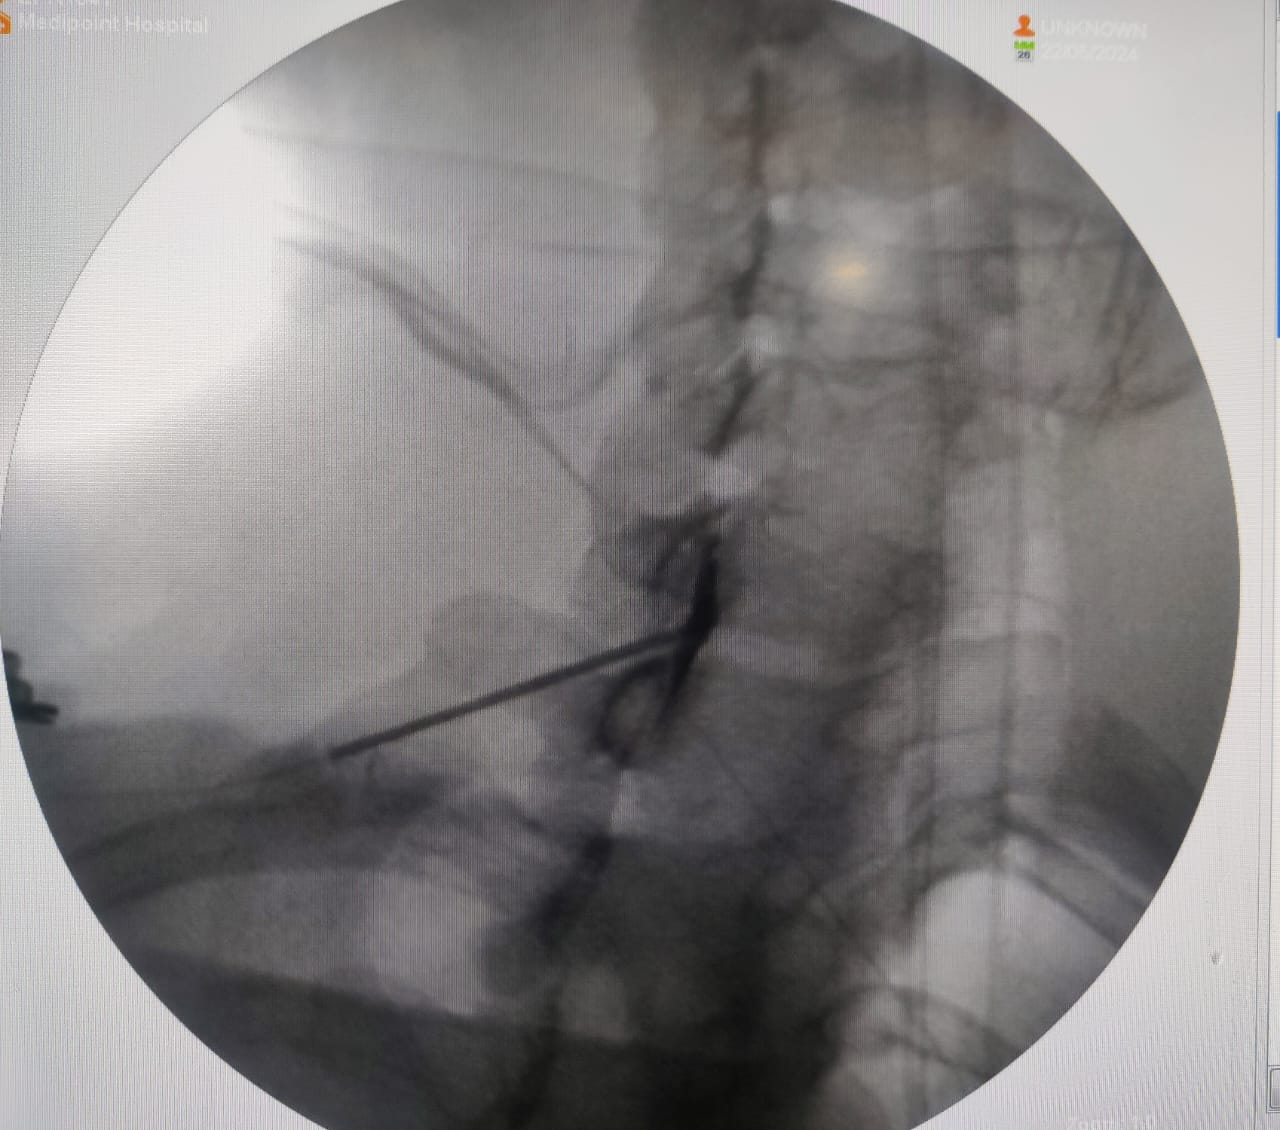

Spine injections, also known as epidural steroid injections or spinal injections, are commonly used to treat various conditions such as chronic back pain, herniated discs, sciatica, and spinal stenosis. General Safety Considerations 1. Qualified pain specialist: It's crucial that the injections are administered by a qualified and experienced pain specialist. Proper technique and knowledge of anatomy significantly reduce the risk of complications. 2. Sterile Technique: Using sterile equipment and maintaining a sterile environment during the procedure are essential to prevent infections. 3. Patient Health: The patient's overall health, including underlying medical conditions and any medications they are taking (especially blood thinners), can impact the safety and suitability of the procedure. Potential Risks and Complications While spine injections are generally safe, they do carry some risks, including: 1. Infection: Although rare, infections can occur at the injection site or, more seriously, in the spine itself. 2. Bleeding: There is a risk of bleeding, especially in patients with bleeding disorders or those taking anticoagulant medications. 3. Nerve Damage: Damage to the nerves can occur, leading to pain, weakness, or sensory changes. However, this is also rare. 4. Dural Puncture: Accidental puncture of the dura (the outer membrane of the spinal cord) can lead to a headache, which is usually temporary but can sometimes be severe. 5. Allergic Reactions: Allergic reactions to the injected substances (such as steroids or local anaesthetics or radio-opaque dye) can occur. 6. Increased Pain: Some patients may experience an increase in pain following the injection, though this is typically temporary. Benefits and Efficacy Spine injections can provide significant pain relief and improved function for many patients, which can be beneficial for those who have not responded to other treatments. The relief can be temporary, lasting from weeks to months, and in some cases, it may help patients avoid surgery or reduce their reliance on oral medications. Conclusion Spine injections are generally considered safe when performed by experienced pain specialists under appropriate conditions. However, as with any medical procedure, there are risks involved. Patients should discuss the potential benefits and risks with their pain specialist to determine if this treatment is appropriate for their specific condition. Are you looking for best doctor for your sciatica / back pain / neck pain ? Do consult our best pain and spine specialist in Pune. Contact number: 9823743726